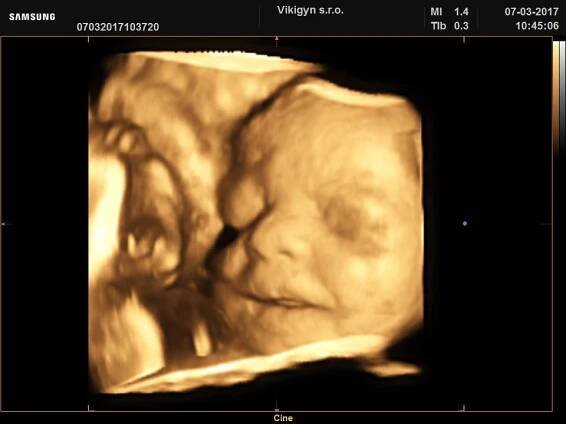

3D ultrazvuk, 20týden, chlapeček :)

Jaký je rozdíl mezi 3D a 4D ultrazvukem?Snímek 3D je dokonale plastická fotografie vašeho miminka, zcela reálná v daném čase a prostoru. V případě 4D zobrazení jde technický pokrok ještě dále a vy máte díky této technologii možnost vidět i reálný pohyb miminka natočený na videozáznam.

3D ultrazvuk je lékařská ultrazvuková technologie, často používaný v porodnické ultrasonografii (během těhotenství), poskytující troj-dimenzionální obrázek plodu. Wikipedie